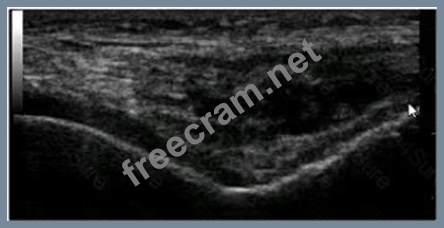

In this image of a knee, what is the MOST obvious abnormality?

Question 39: In this image of a knee, what is the MOST obvious abnormalit...